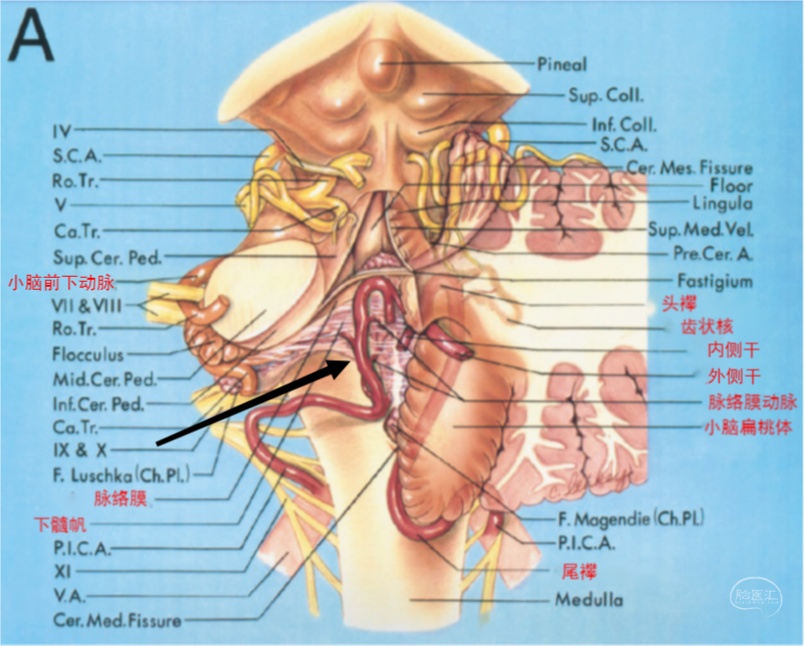

图3 小脑后下动脉后面观,图中黑箭所示为脉络膜附着于延髓的脉络带,同时也是四脑室的下界,为扁桃体延髓段与膜帆扁桃体段的分界点。膜帆扁桃体段发出脉络膜动脉供应第四脑室顶壁中线及外侧隐窝内侧的脉络丛,颅襻部位可发出分支供应齿状核。小脑前下动脉发出脉络膜动脉供应外侧隐窝外侧的脉络丛,与小脑后下动脉之间可形成吻合。